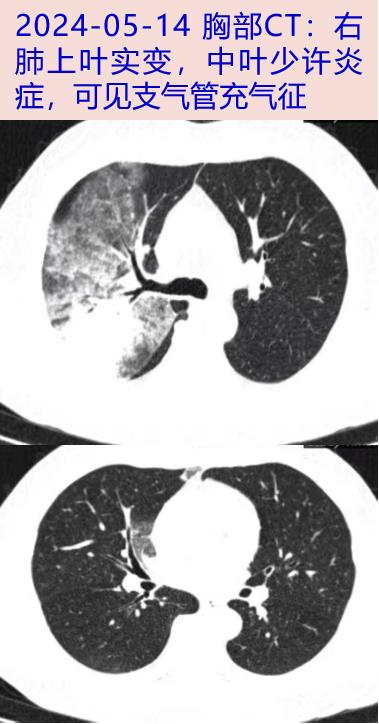

2024-05-14 仍有高热,Tmax 39℃,伴干咳,咳黄粘痰。到我院门诊查看WBC 6.07×109/L,N 70.6%,LY 21.2%;hsCRP 102.2mg/L。胸部CT平扫:右上肺大片实变,内见支气管充气征。中山医院感染科为明确肺炎病因,2024-05-15收益。

2024-5-20 体温平整,乏力好转,无干咳、咳痰,复查WBC。 3.6×109/L,N 59.1%,L 1.1×109/L;hsCRP 36.5mg/L,ESR 28mm/h,PCT 0.04ng/mL,ALT/AST 32/28U/L,Alb 35g/L,NT-proBNP 290pg/mL。hsCRP、AST、NT-proBNP较前降低,淋巴细胞计数,Alb较前升,胸部CT:右肺上叶发炎,比05-14明显吸收,出院。